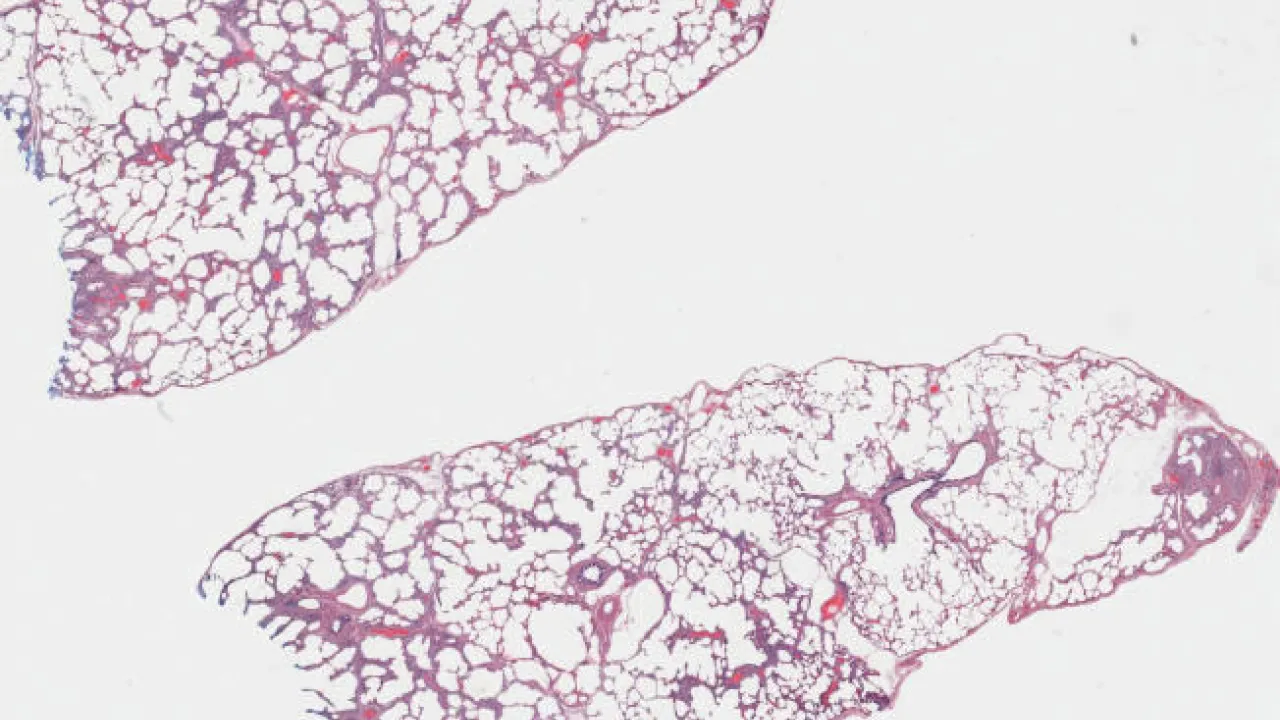

Lung, Nonspecific interstitial pneumonia, cellular pattern